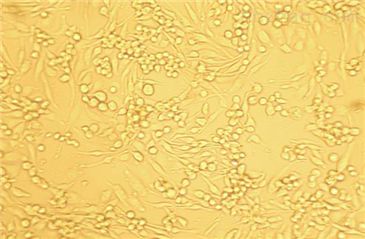

HT29(人结肠癌细胞)复苏

贴壁生长